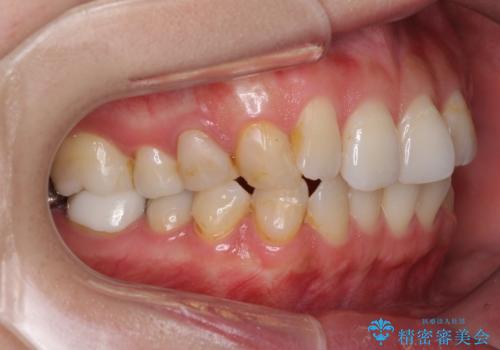

- 失活により変色した歯と不揃いな口元を気にして来院された患者様です。

口元をインビザラインにより歯列を整え、その後に失活している奥歯をオールセラミッククラウンにて補綴治療することとしました。